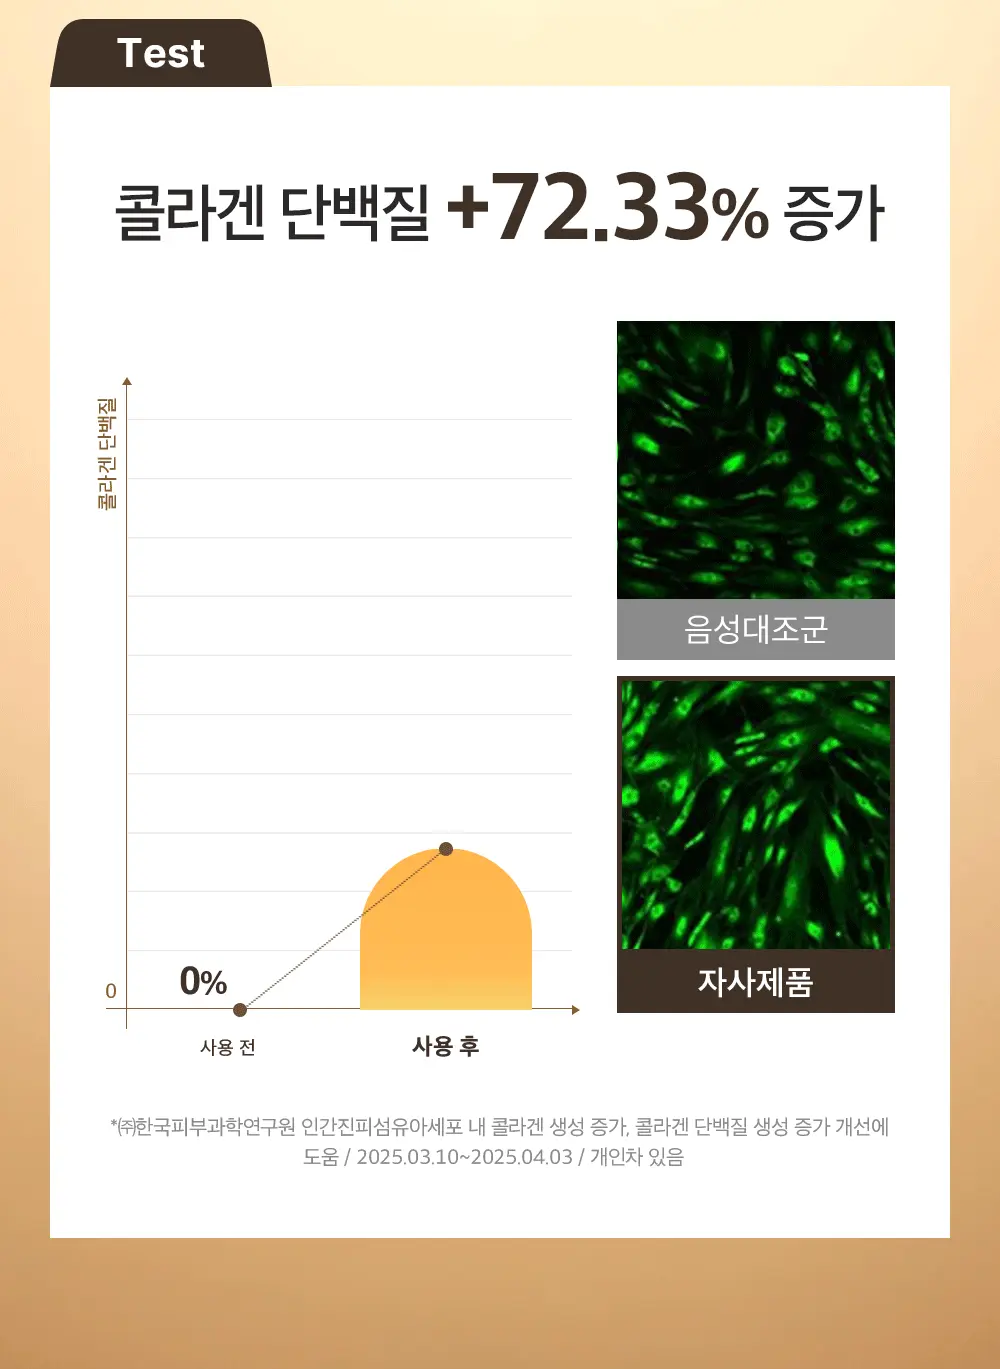

成效數據

額部皺紋起始處提升率:83.57%

臉頰深層脂肪突出處提升率:82.11%

嘴角凹陷處提升率:56.73%

下巴皮膚皺摺處提升率:51.64%

眼周易生皺紋處提升率:47.37%

✔️ 加入更先進的抗老成分EGF,新增成分9GF,一種基於EGF的豐盈提拉成分

✔️ 提升核心成份絲素蛋白勝肽含量(比現有產品高1586倍)

✔️ 高效成分的精確組合,不僅能改善內部彈性、淡化細紋,還能提升中臉部輪廓、補充臉部容量。

- 高濃度蠶絲相關成分:含 68% 絲蛋白胜肽Silk Peptide,比既有配方,含量提升 1,586 倍。

- 注重「膠原蛋白填充感」:能為凹陷或鬆弛處補充膠原蛋白,帶出「3D 塑型/飽滿感」的視覺效果。